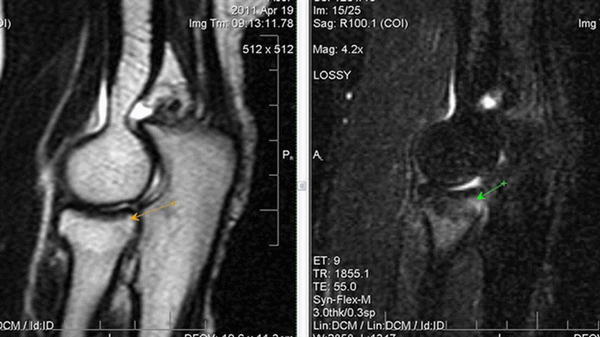

а) МРТ локтевого сустава в аксиальной плоскости

б)МРТ локтевого сустава в корональной плоскости. Общее сухожилие разгибателей в месте прикрепления к латеральному надмыщелку плечевой кости неравномерно утолщено, МР-сигнал от него неоднородно повышен на PD FS-ВИ и Т2-ВИ за счет выраженного отека и разволокнения (признаки латерального эпикондилита), общая целость его не нарушена. Окружающие мягкие ткани с признаками отека.